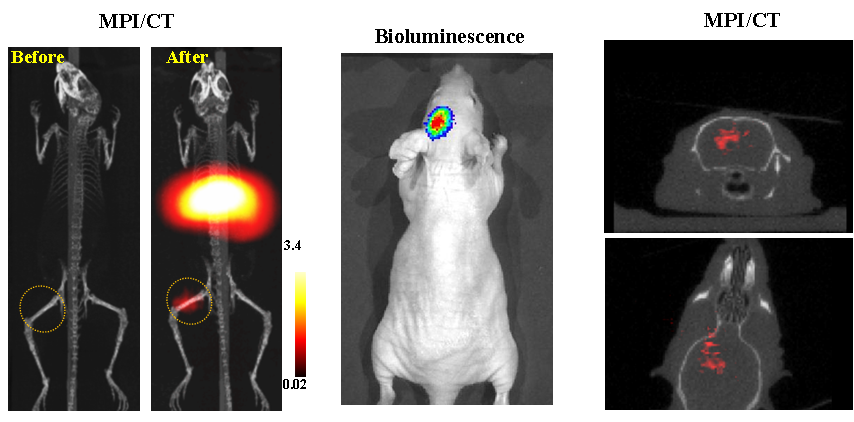

今年二月份,宋国胜教授与斯坦福大学饶江宏教授合作,通过系统的研究获得了影响磁性粒子成像信号的作用规律和关键原理,开发了新型磁性粒子探针---FeCo合金粒子,并首次应用于磁性粒子成像(MPI)。该造影剂在极低含量时(5 ng)仍具有很强的造影效果。这意味着,未来在进行人体成像时,可以使用更小剂量的造影剂,从而避免高剂量造影剂引起的肾肝损伤。基于MPI的直接成像原理,我们可以对造影剂进行正相和无背景干扰的活体成像,极大地提高信噪比。这项技术为肿瘤早期诊断、癌细胞示踪、脑中风、药物输送治疗、肺部灌注成像、胃肠出血、神经退行性疾病、磁热治疗等在活体中的可视化研究,提供了强有力的手段。相关研究成果以玩偶姐姐

为第一单位发表在Nature 子刊《Nature Biomedical Engineering》。该期刊是“生物医学工程”的顶级期刊。宋国胜教授为该论文的共同通讯作者。